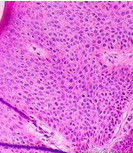

本病組織病理學上高度分化的鱗狀上皮細胞內瘤變或原位鱗狀細胞癌,其特徵為表皮細胞結構混亂,有很多核大、深染、成堆的異形的鱗狀上皮細胞,可見病理性核分裂象。真皮乳頭層水腫,毛細血管彎曲擴張,周圍有慢性炎症細胞浸潤。治療